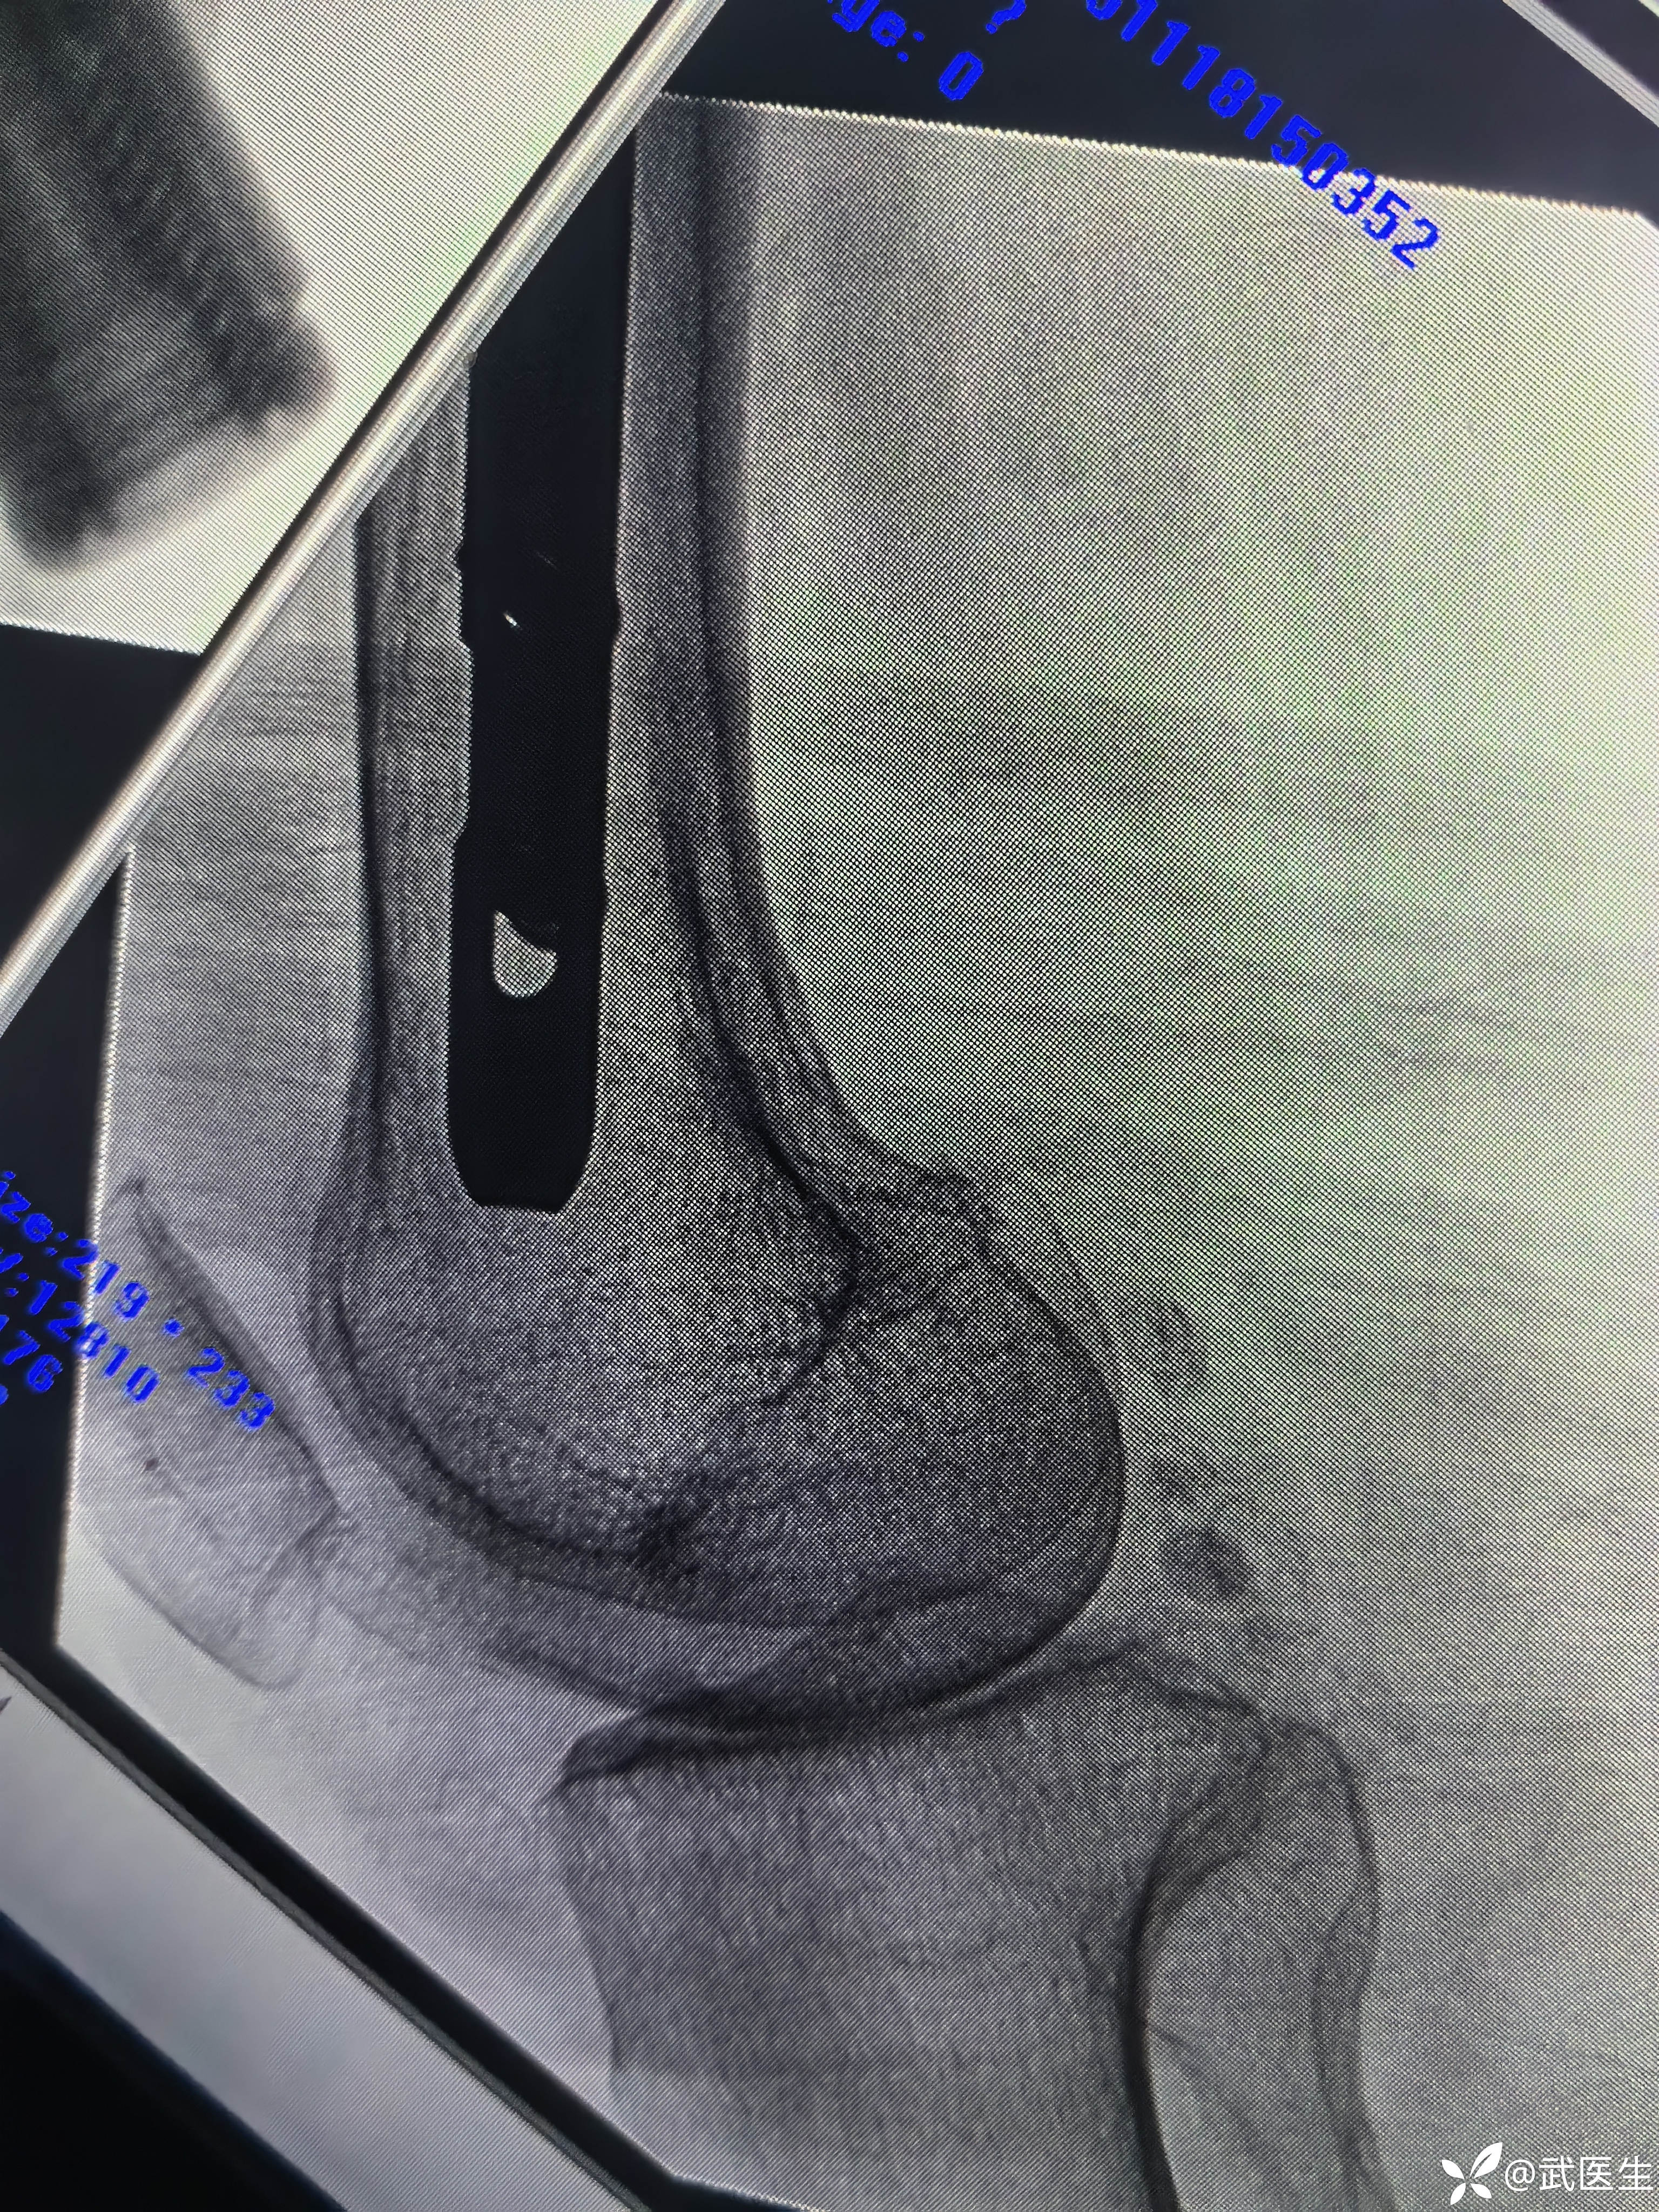

打头颈导针

正位,头颈导针居中偏下,可以

轴位,居中略偏前,能接受

这个轴位,又好了,不错,应该是投照角度问题,本来就好。